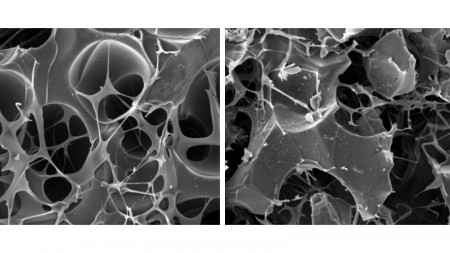

Microscopic images of the structure of the biomaterials tested for fracture healing during the study. On the right is a carbon matrix, and on the left is the same matrix combined with nanographite (image: Daniela Franco Bueno et al.)

For this process to occur, the microarchitecture of the biomaterials must be regulated to have pores of sizes and connections that allow blood vessels and cells to enter and nutrient exchange to occur. Properties such as stiffness and strength must also be considered to ensure compatibility with bone. Laboratory production methods and 3D printing control all of this.